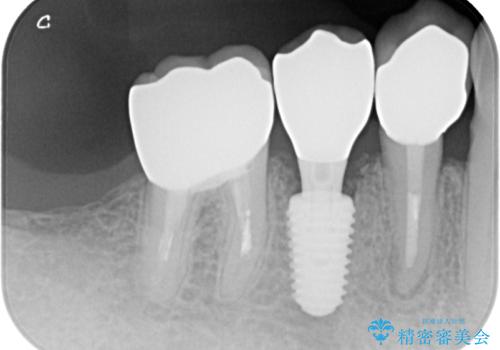

- 奥歯に装着していたクラウンが外れてしまったとのことで来院された患者様です。

診察したところ、歯根に破折線が確認され抜歯が必要な状態でした。

歯肉や歯槽骨の状態は良好であったため、抜歯即時埋入インプラントによる補綴治療を行うこととしました。

抜歯、インプラント埋入、仮歯の装着を1度に行うことができ、治療終了までわずか3か月で終えることができました。